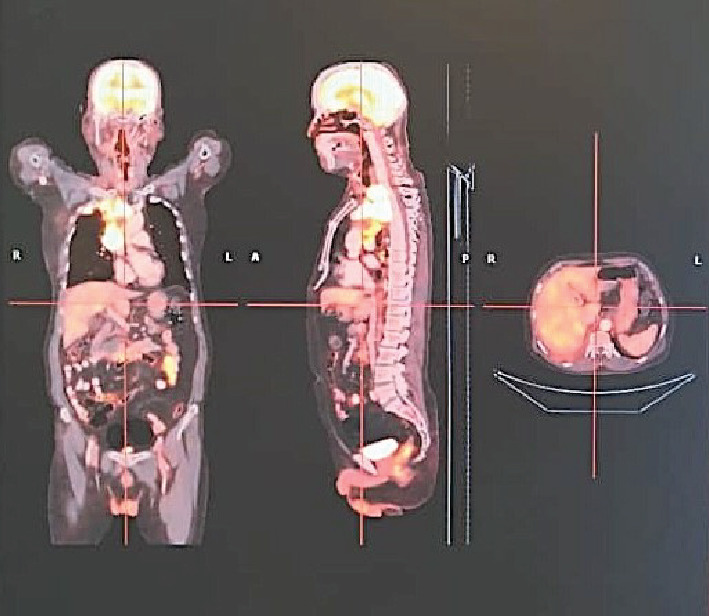

大细胞神经内分泌癌(LCNEC)是一种罕见的侵袭性癌症,主要发生在肺部,但也可以发生在其他器官。它的特点是进展迅速和高转移潜力。我们提出一例晚期LCNEC肺患者表现不佳(PS),需要氧气支持。影像学显示右上叶大肿块,淋巴结病变,伴支气管包膜及侵犯上腔静脉,导致SVC综合征及胸腔积液。活检和免疫组化证实LCNEC。由于患者PS较差,以低剂量单药化疗(卡铂)开始治疗,改善后给予依托泊苷和顺铂治疗。同时给予局部放疗,并调整治疗计划纳入atezolizumab。10个周期后,患者完全缓解,持续6年。该病例强调了老年患者晚期LCNEC管理的复杂性以及多学科方法和免疫治疗的有效性。

Large cell neuroendocrine carcinoma (LCNEC) is a rare, aggressive cancer primarily found in the lungs but can also occur in other organs. It is characterized by rapid progression and high metastatic potential. We present a case of advanced-stage LCNEC lung in a patient with a poor performance status (PS), requiring oxygen support. Imaging revealed a large right upper lobe mass, lymphadenopathy, with bronchial encasement and invasion into the superior vena cava, leading to SVC syndrome and pleural effusion. Biopsy and immunohistochemistry confirmed LCNEC. Due to the patient's poor PS, treatment began with low-dose single-agent chemotherapy (carboplatin), followed by etoposide and cisplatin after improvement. Local radiation was also administered, and the treatment plan was adjusted to include atezolizumab. After 10 cycles, the patient achieved complete remission, sustained for 6 years. This case highlights the complexities of managing advanced LCNEC in a geriatric patient and the effectiveness of a multidisciplinary approach and immunotherapy.